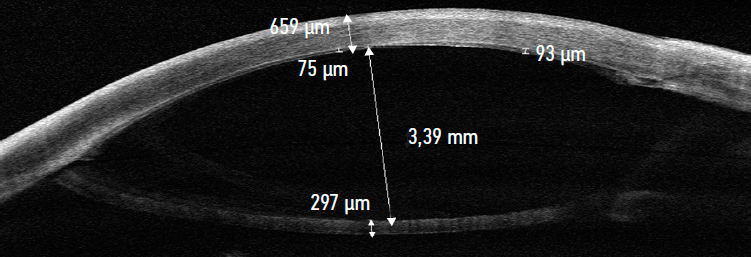

Both patients had no complications characteristic of endothelial keratoplasty, including graft dehiscence, early graft failure, significant and progressive local diastases, and pupillary block, in the early postoperative period. It took no more than 2 days for the air to dissipate in the anterior chamber in both cases. When the air bubble dissipated, the stromal flap located between the remaining lens-iris diaphragm and endothelial graft (Fig. 3, 4). On day 3, the BSF was removed in the operating room. Intraoperative OCT control showed no endothelial graft dehiscence during the BSF removal from the anterior chamber.

Fig. 4. Clinical case No. 2. OCT of the cornea, day 3 after modified femtosecond laser-assisted posterior automated lamellar keratoplasty with a banded stromal flap. The central thickness of the cornea is 659 µm, there are no diastases of the endothelial graft, the banded stromal flap in the anterior chamber of the eye in a free position, there is no contact of the banded stromal flap with the posterior surface of the endothelial corneal graft, the thickness of the banded stromal flap is 297 µm

Рис. 4. Клинический случай № 2. Оптическая когерентная томография роговицы, 3-и сутки после модифицированной фемто-ассистированной задней автоматизированной послойной кератопластики с бандажным стромальным лоскутом. Центральная толщина роговицы 659 мкм, диастазы эндотелиального трансплантата отсутствуют, бандажный стромальный лоскут в передней камере глаза в свободном положении, отсутствие его контакта с задней поверхностью эндотелиального трансплантата роговицы, толщина бандажного стромального лоскута 297 мкм